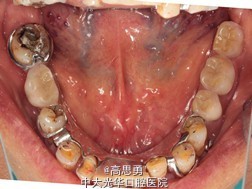

检查(包括专科检查及辅助检查): 1、全身状况良好,无全身系统性疾病,自主行动能力正常。精神心理状态无异常。 2、颌面部左右对称,面部比例协调,面部正面形态尖圆形。颞下颌关节运动无异常,开口型无异常,颞下颌关节无弹性,无压痛。 3、口内黏膜未见瘢痕,舌运动无异常。唇颊系带附着无异常,唾液分泌无异常。 4、牙龈正常,无肿胀无瘘管。 5、口内检查: #32近中移位约1mm,无明显倾斜 #44远中移位约2mm,向缺隙侧倾斜,伸长约1mm 其余缺牙间隙正常 全口牙龈退缩至根颈1/3,牙龈无肿胀无瘘管 上颌缺牙区牙槽嵴无明显吸收、下颌缺牙区牙槽嵴吸收呈低平刃状 口腔卫生状况欠佳、全口牙石多 11 12 13 14 15 16 17 21 22 23 24 25 26 27 视 存 存 存 缺 缺 缺 缺 存 存 存 缺 缺 缺 存 探 - - + - - - - - - - - - - - 叩 - - + - - - - - - - - - - - 松 - - I° - - - - - - - - - - - 楔 O O O - - - - O O O - - - - 31 32 33 34 35 36 37 41 42 43 44 45 46 47 视 缺 存 存 存 缺 缺 缺 缺 存 存 存 缺 缺 存 探 - - - - - - - - - - - - - - 叩 - - - - - - - - - - - - - - 松 - - - - - - - - - - - - - - 楔 - - O - - - - - O O O - - - 根尖X片示:13 根尖部阴影,牙颈部硬组织部分缺损 转诊牙体牙髓科后复诊 修复科第二次就诊口内检查: 11、12、13、21、22、23、33、42、43、44牙颈部见黄色充填物 13 探(-)、叩(-)、松(-),HE面见白色暂封物 口腔卫生状况尚可、牙石少,其余牙叩(-)、松(-) 根尖X片示:13 根尖部阴影,根充可 其余同前

诊断: 1、牙列缺损(上颌肯氏II类I分类,下颌肯氏II类II分类) 2、#13慢性根尖周炎 3、#11、#12、#13、#21、#22、#23、#33、#42、#43、#44楔状缺损 4、慢性牙周炎 治疗计划 1、#13转牙体牙髓科做RCT 2、转牙体牙髓科对#11、#12、#13、#21、#22、#23、#33、#42、#43、#44楔状缺损 充填治疗 3、转牙周科进行牙周洁治 4、择期RPD修复 备选修复方案: 1、#13RCT后截冠后,上下颌覆盖义齿修复; 2、#13RCT后冠修复,上下颌可摘局部义齿修复; 3、#13RCT后树脂充填,上下颌可摘局部义齿修复; 4、#13拔除后,上下颌可摘局部义齿修复。 患者意愿:患者希望尽量保持#13的天然形态,要求费用尽量低,但能恢复正常咀嚼功能。 最终治疗方案:根据患者的年龄、身体状况、治疗周期、经济状况,患者最终选择方案5,即#13RCT后树脂充填,上颌结合卡环式可摘局部义齿修复;下颌可摘铸造支架式局部义齿修复。 治疗过程: 1、临床检查和#13树脂充填 对患者进行全面的口腔检查,用Z350树脂充填#13,调HE,抛光。 2、研究模型 调拌藻酸盐印模材料于2号成品托盘上取上下颌研究模,灌注石膏模型,研究分析、制定治疗计划,并制作个别托盘。 3、基牙预备 对#13近中、#23远中、#27近中、#34近中、#47近中常规制备支托凹,抛光。 4、工作模型 调拌藻酸盐印模材料于个别托盘上。做一定的边缘整塑,取上下颌研究模,灌注石膏模型。 5、试戴支架 检查支架的就位、固位可,无翘动,调HE,抛光,用蜡堤取颌位关系,上颌架,排牙,比色C4。 6、试排牙 检查义齿的就位、固位可,无翘动,观察人工牙的咬合状况,尖窝接触良好,正中颌位能重复,患者无诉不适,面容自然,外观满意。送加工厂充胶制作最终修复体。 7、试戴 检查义齿的就位、固位可,无翘动,咬合关系正确,利用咬合纸检查,上下颌尖窝接触均匀全面,抛光,患者表示满意,嘱注意事项,定期复诊。